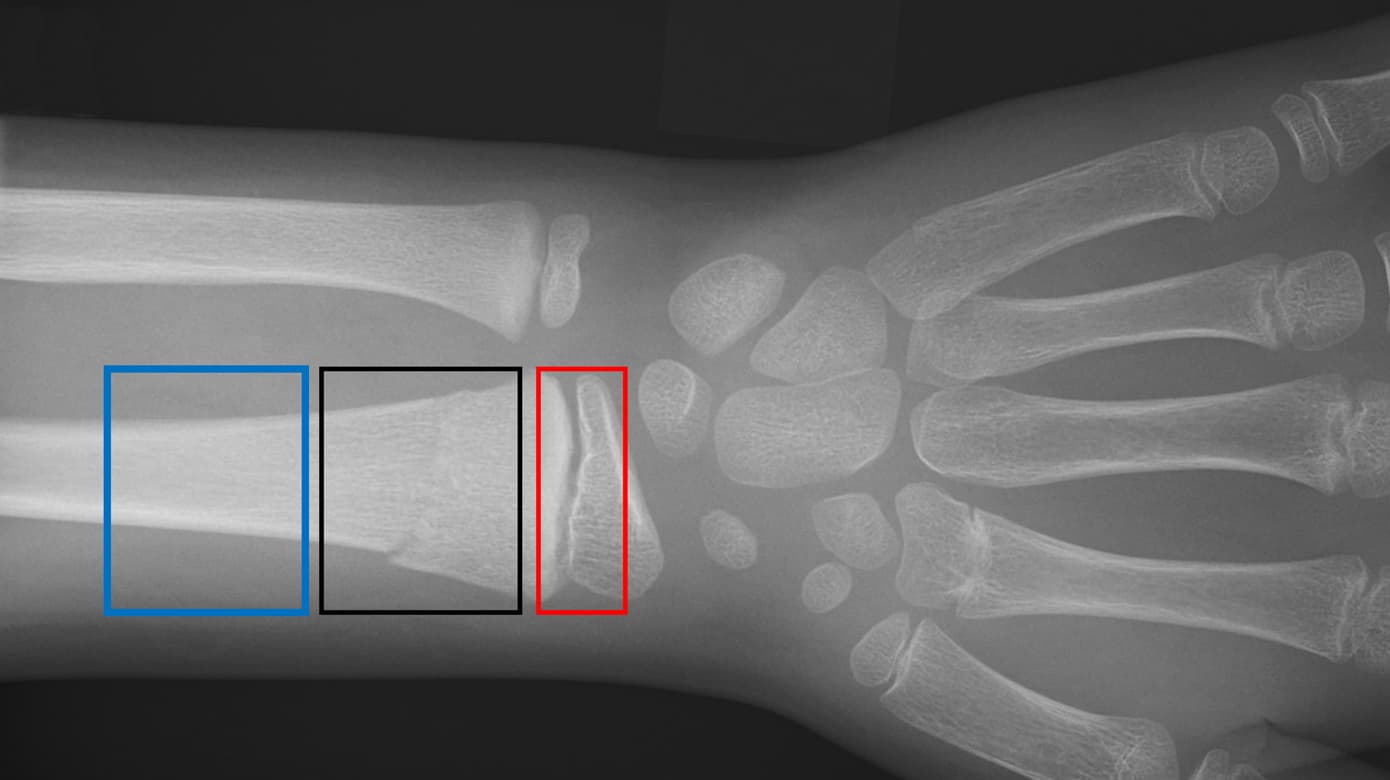

Frakturerne inddeles i epifysiolyser, metafysære og metadiafysære frakturer samt i inkomplette (»torus«-, »buckle«- og »green-stick«-fraktur) og komplette frakturer (Figur 1). Børn har under vækst stor remodelleringsevne, og 75% af længdevæksten og dermed størstedelen af remodelleringen foregår distalt i radius [7]. Evnen til remodellering afhænger af væksthastighed i vækstzonen, restvækst og frakturens afstand fra vækstzonen. Jo tættere frakturen er på vækstzonen, og jo yngre barnet er, des større er remodelleringen. Figur 2 viser et barns evne til at remodellere over tid.